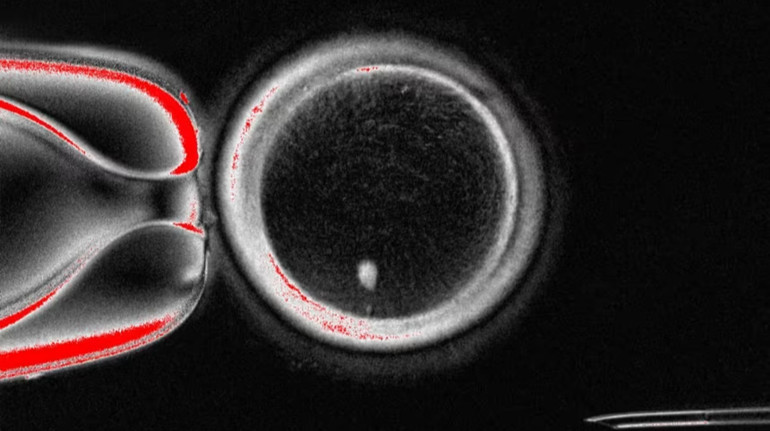

Photo: Mitalipova laboratory

In total, scientists have created 82 functional oocytes – immature eggs, which were subsequently fertilized in the laboratory.